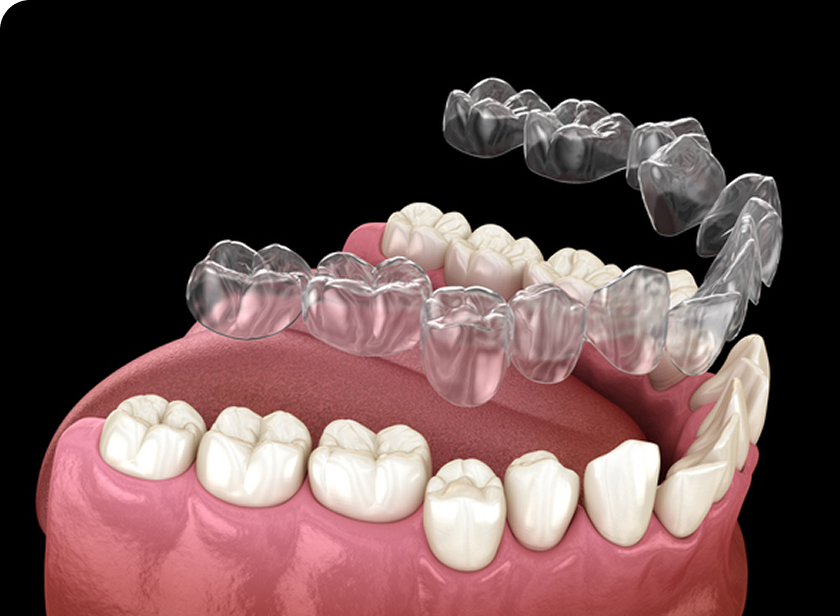

인비절라인(Invisalign)은 눈에 띄지않게 투명하게 제작된 교정 장치입니다.

치아 상태에 맞게 디지털 장비로 맞춤 설계된 투명 교정 장치를 주기적으로 교체하며 치아를 서서히 이동시키는 방식으로 진행됩니다.

기존의 금속 교정 장치와 달리 뛰어난 심미성으로

티나지 않는 교정을 원하시는 경우 적합하며 탈부착이 가능하여 위생관리가 편안합니다.